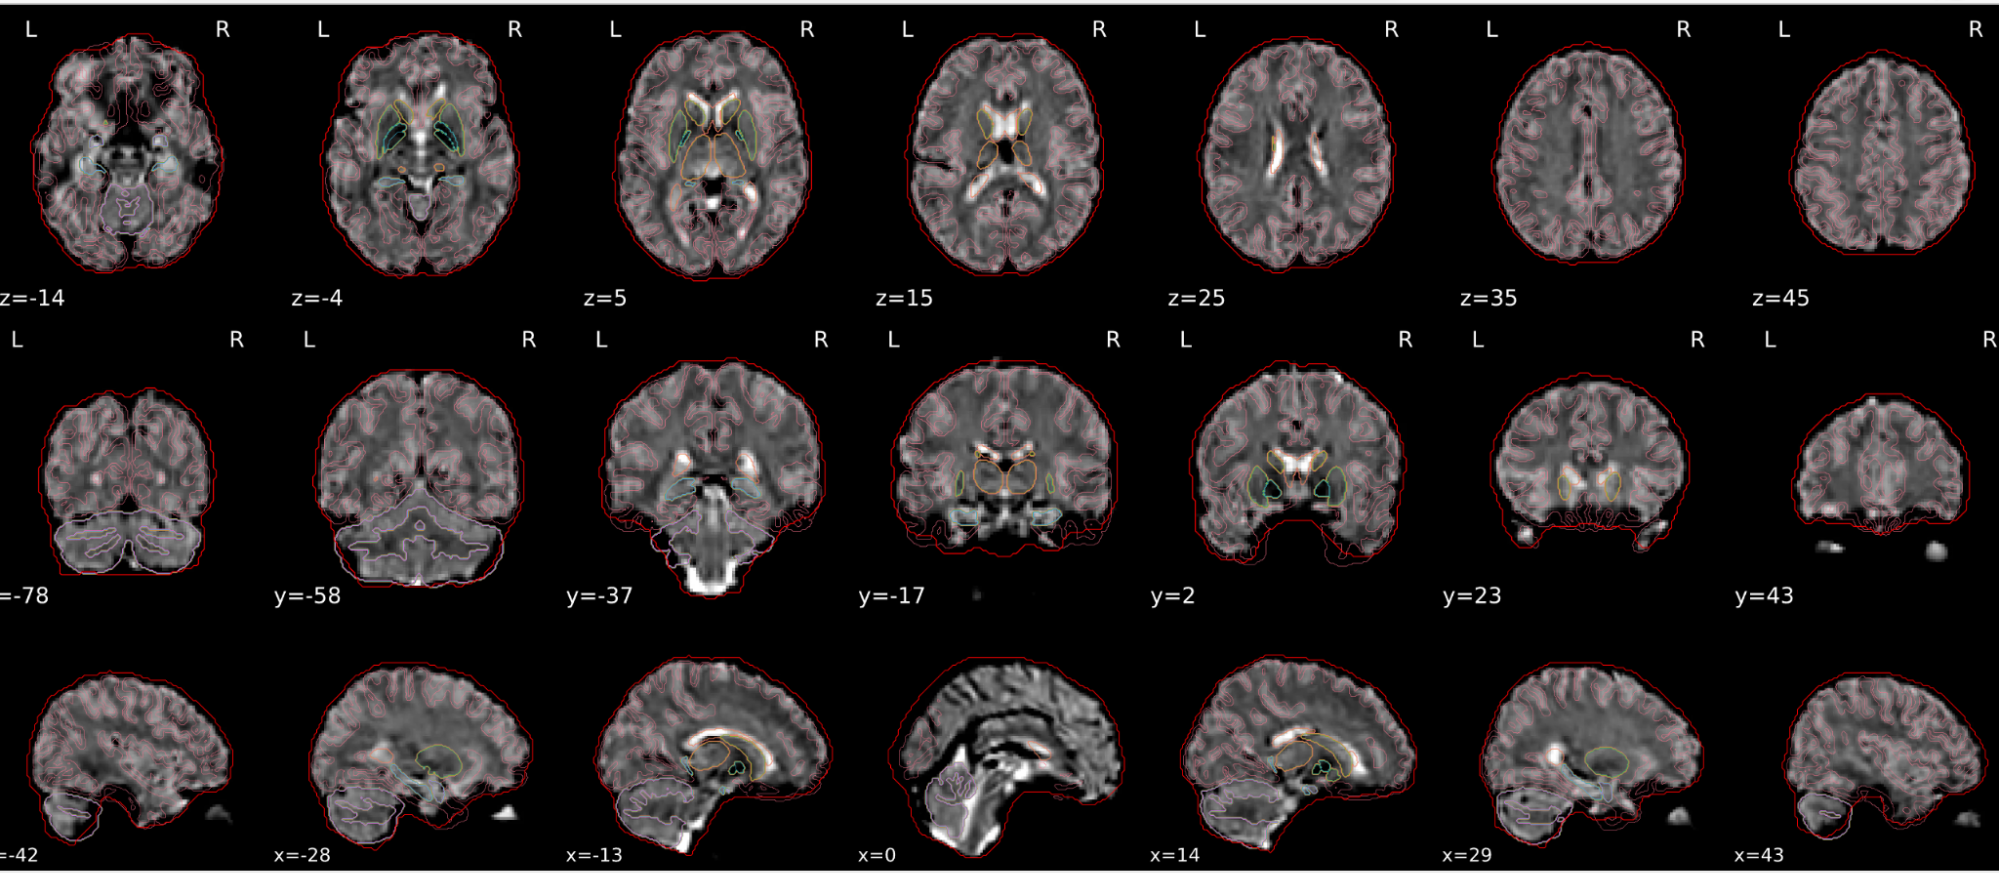

EPI spatial normalisation

This QC step shows the registration of the EPI image to MNI space.

Example of a good subject

- If the registration performed well, you should see an overlap (i.e., correspondence of structures) between the MNI template and the EPI registered to the MNI space.

- If parts of the brain are missing due to the scanner field of view, this is fine. For example, the cerebellum may be cut off for a participant with a large head.

Example of a bad subject

- In case of poor registration, you should see a misalignment of the EPI and the MNI template

Summary

| good | bad |

|---|---|

| Overlap (i.e. match of structures) between the MNI template and the EPI registered in the MNI space | Misalignment of the EPI and the MNI template |

| If parts of the brain are missing because the field of view of the scanner is limited, the EPI spatial normalisation does not have to be excluded e.g. cerebellum cut off in person with large head |

If parts of the brain are missing because the field of view of the scanner is limited, the EPI spatial normalisation does not have to be excluded (e.g. cerebellum cut off in person with large head)